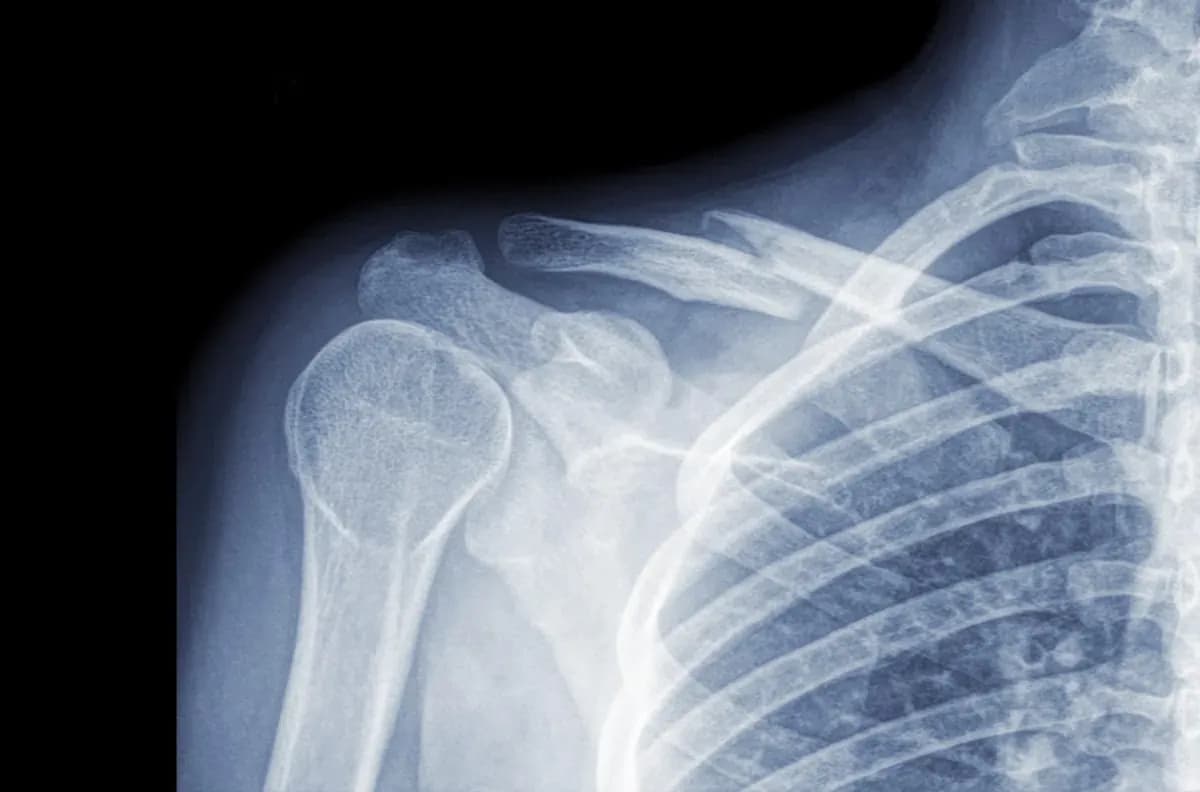

Ile trwa rehabilitacja po złamaniu obojczyka i co wpływa na czas?

Ile trwa rehabilitacja po złamaniu obojczyka? Sprawdź, jakie czynniki wpływają na czas powrotu do zdrowia i jak przyspieszyć proces rehabilitacji.